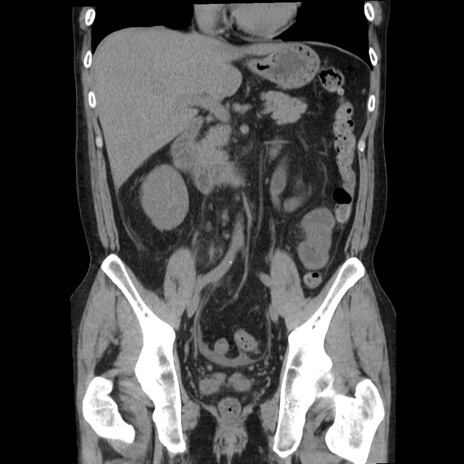

横断像

【症例】40歳代男性

【現病歴】2日前から胃痛あり。徐々に周期的な激痛に変化した。本日になっても激痛があるため受診。

【身体所見】意識清明、BT 38-39℃台あり、腹部:膨満、やや硬、右下腹部に圧痛あり。

【データ】WBC 8500、CRP 23.26